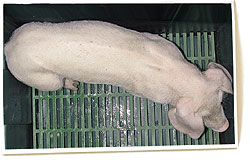

Porc de 3 mois atteint de MAP. On remarque l'épine dorsale marquée, signe de retard de croissance, et la pâleur corporelle (anémie).